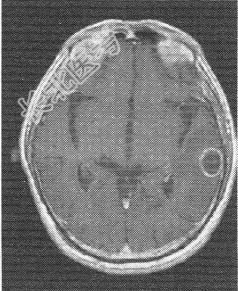

- 单项选择题患者男,72岁。肺癌术后一年余, 现出现头晕头痛,MR图像如下, 最具有可能的诊断是

B、脑转移癌